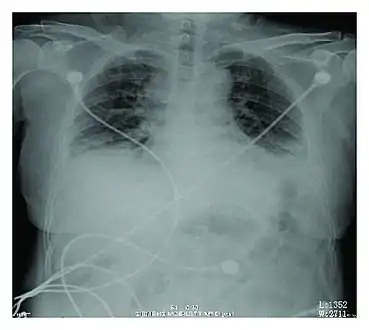

Rapid progression from initial symptoms to respiratory failure is a key feature. An X-ray that shows ARDS is necessary for diagnosis (fluid in the small air sacs (alveoli) in both lungs). In addition, a biopsy of the lung that shows organizing diffuse alveolar damage is required for diagnosis. This type of alveolar damage can be attributed to nonconcentrated and nonlocalized alveoli damage, marked alveolar septal edema with inflammatory cell infiltration, fibroblast proliferation, occasional hyaline membranes, and thickening of the alveolar walls. The septa are lined with atypical, hyperplastic type II pneumocytes, thus leading to the collapse of airspaces. Other diagnostic tests are useful in excluding other similar conditions, but history, X-ray, and biopsy are essential. These other tests may include basic blood work, blood cultures, and bronchoalveolar lavage. The clinical picture is similar to ARDS, but AIP differs from ARDS in that the cause for AIP is not known.

Acute interstitial pneumonia showing a marked reduction in lung capacity